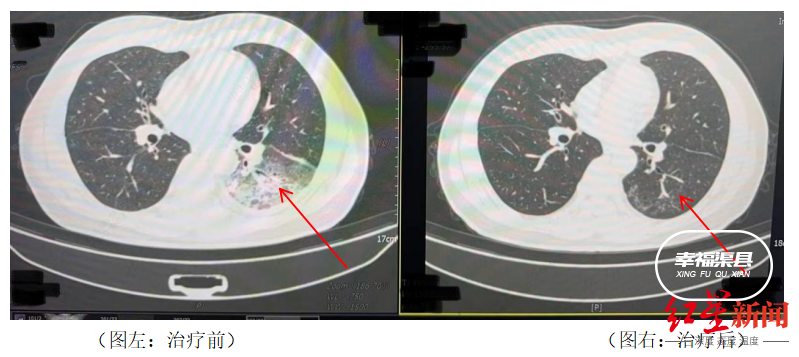

据悉,开启空调降温3天后,李先生出现了肌肉酸痛、头痛、发热和咳嗽等症状。起初,他以为是吹空调吹感冒了,于是自行服用感冒药,但病情并未好转,反而愈发严重。家人见状,立即将他送往成都市第五人民医院感染性疾病科。胸部CT显示李先生的左肺已出现大面积白色影像,几乎占据一半肺部。经过肺泡灌洗NGS检测,最终确认“罪魁祸首”是嗜肺军团菌。